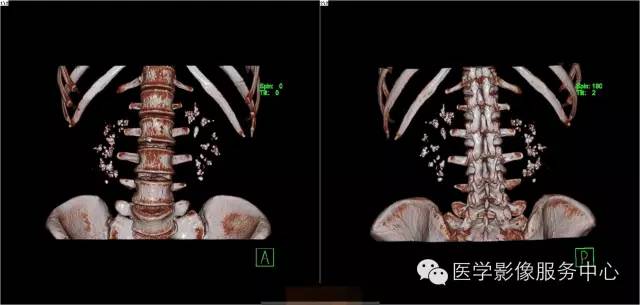

髓质海绵肾(简称MSK)又称Cacchi Ricci disease,是一种先天发育性肾髓质囊性病变,发生率约1:2000-5000,多见于40-60岁男年,70%为双侧肾脏发病,病变局限于髓质范围内,常累及两侧肾的多数锥体和乳头,形成许多数毫米的囊腔使髓质如海绵状,故名海绵肾,病理特点为集合管远端扩张,形成圆形或不规则型囊腔,囊内壁衬以立方或扁平上皮,囊内充溢脱离的上皮及钙化形成的小结石。

3、CT平扫表现一个或多个肾锥体内散在或蔟团状多发结石,呈花瓣样或扇形分布;部分腹部平片阴性,CT平扫可发现肾锥体内细小的结石。增强扫描表现扩张的肾集合管内有条纹状、刷状、小囊状或扇形的造影剂浓聚。部分患者肾实质内可见多发小囊肿。